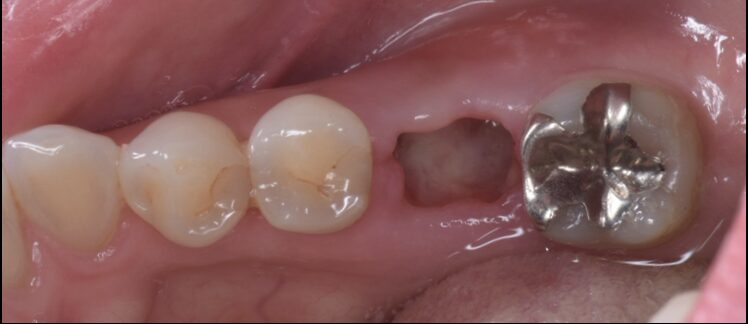

奥歯破折により抜歯後、インプラント治療した症例

Before